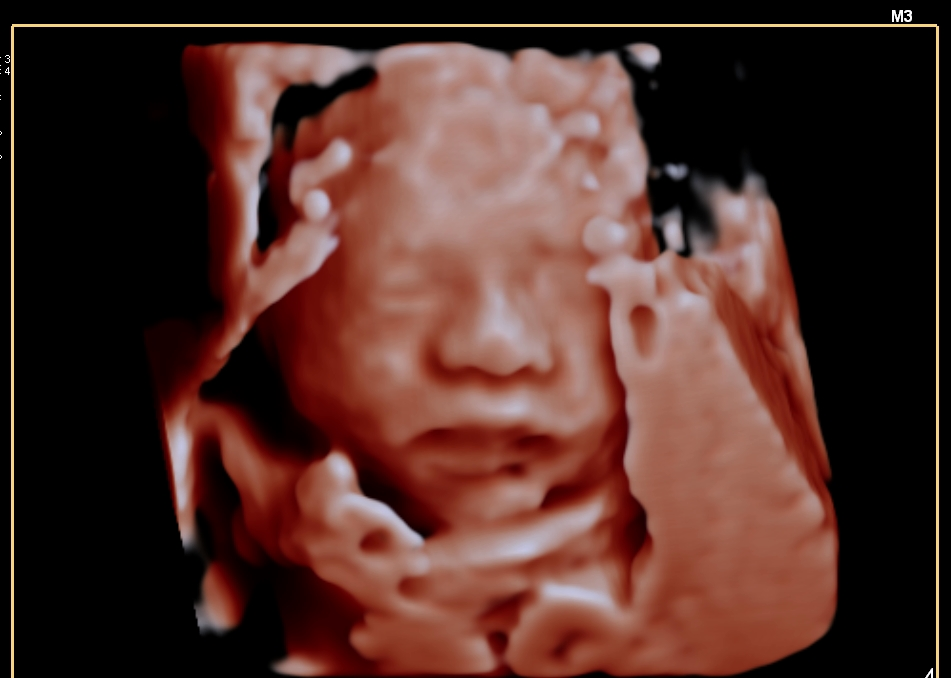

四维彩超就像是给宝宝在子宫里拍的一段 “动态3D电影” 。它能够让准爸爸准妈妈们清晰地看到宝宝在肚子里的实时动态,比如打哈欠、吃手指、微笑、翻身等,为孕期增添了许多惊喜和温情。

2. 次要目的:满足情感需求

让准父母亲眼看到宝宝的活动,建立早期的亲子连接。可以拍摄照片和视频,作为一份珍贵的纪念。